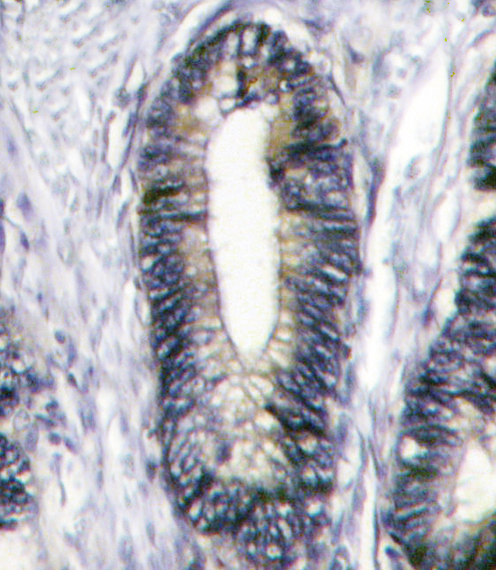

IHC (Immunohistochemisry)

(Formalin-fixed and paraffin-embedded human breast carcinoma tissue reacted with EphB2 antibody (C-term), which was peroxidase-conjugated to the secondary antibody, followed by DAB staining. This data demonstrates the use of this antibody for immunohistochemistry; clinical relevance has not been evaluated.)